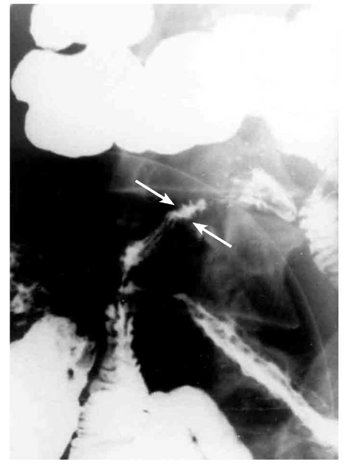

האבחון הרנטגני הוא חשוב. צילום בליעת בריום, אנטרוקליזיס וטומוגרפיה ממוחשבת של הבטן עם בליעת חומר ניגוד הם הכלים העיקריים לאבחנה. קשת של סימנים מצביעה על פתולוגיה במעי הדק.

- הסימן האופייני הוא ה-String sign, המבטא התעבות של דופן המעי והיצרויות של נהור המעי (תצלום 14.4).

- המעי נוקשה - Lead pipe (תצלום 16.4).

- הרירית מאבדת את המבנה הרגיל שלה ואפשר לזהות בה פיסורות, תבנית אבני מרצפת, חריגויות ואי-סימטריה (תצלום -17.4 ו-18.4).